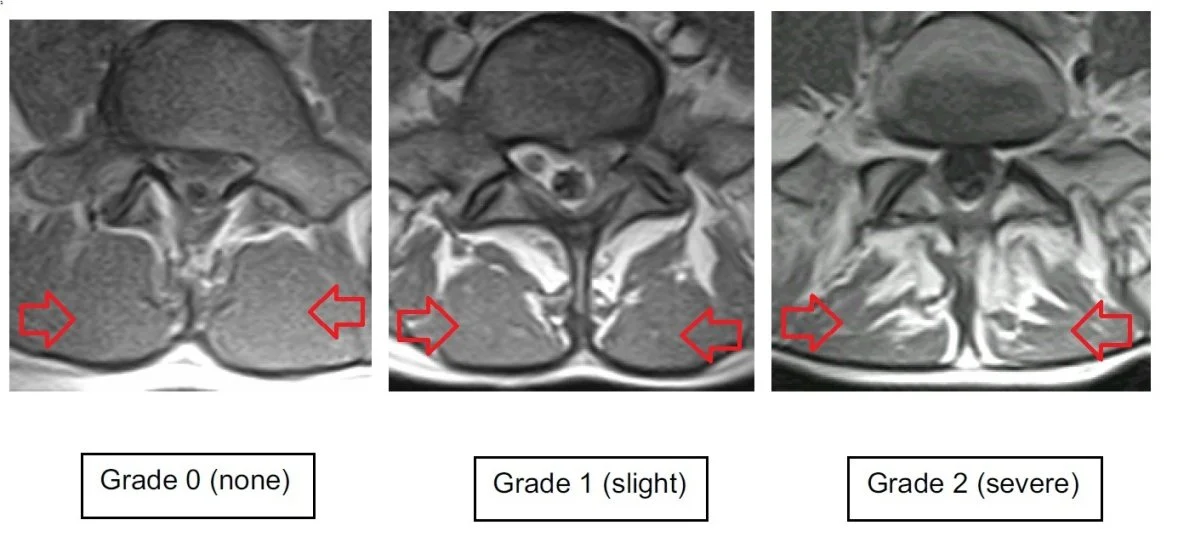

This image is directly from the referenced journal article. The multifidus are indicated with red arrows and the above image shows normal lumbar multifidus (Left), slight fatty infiltration (Middle) and severe fatty infiltration (Right). So when you’re next working out, sitting on the couch or getting adjusted, think about what is happening to your multifidus. As we said last week, like any muscle if you don’t use it, you will lose it!